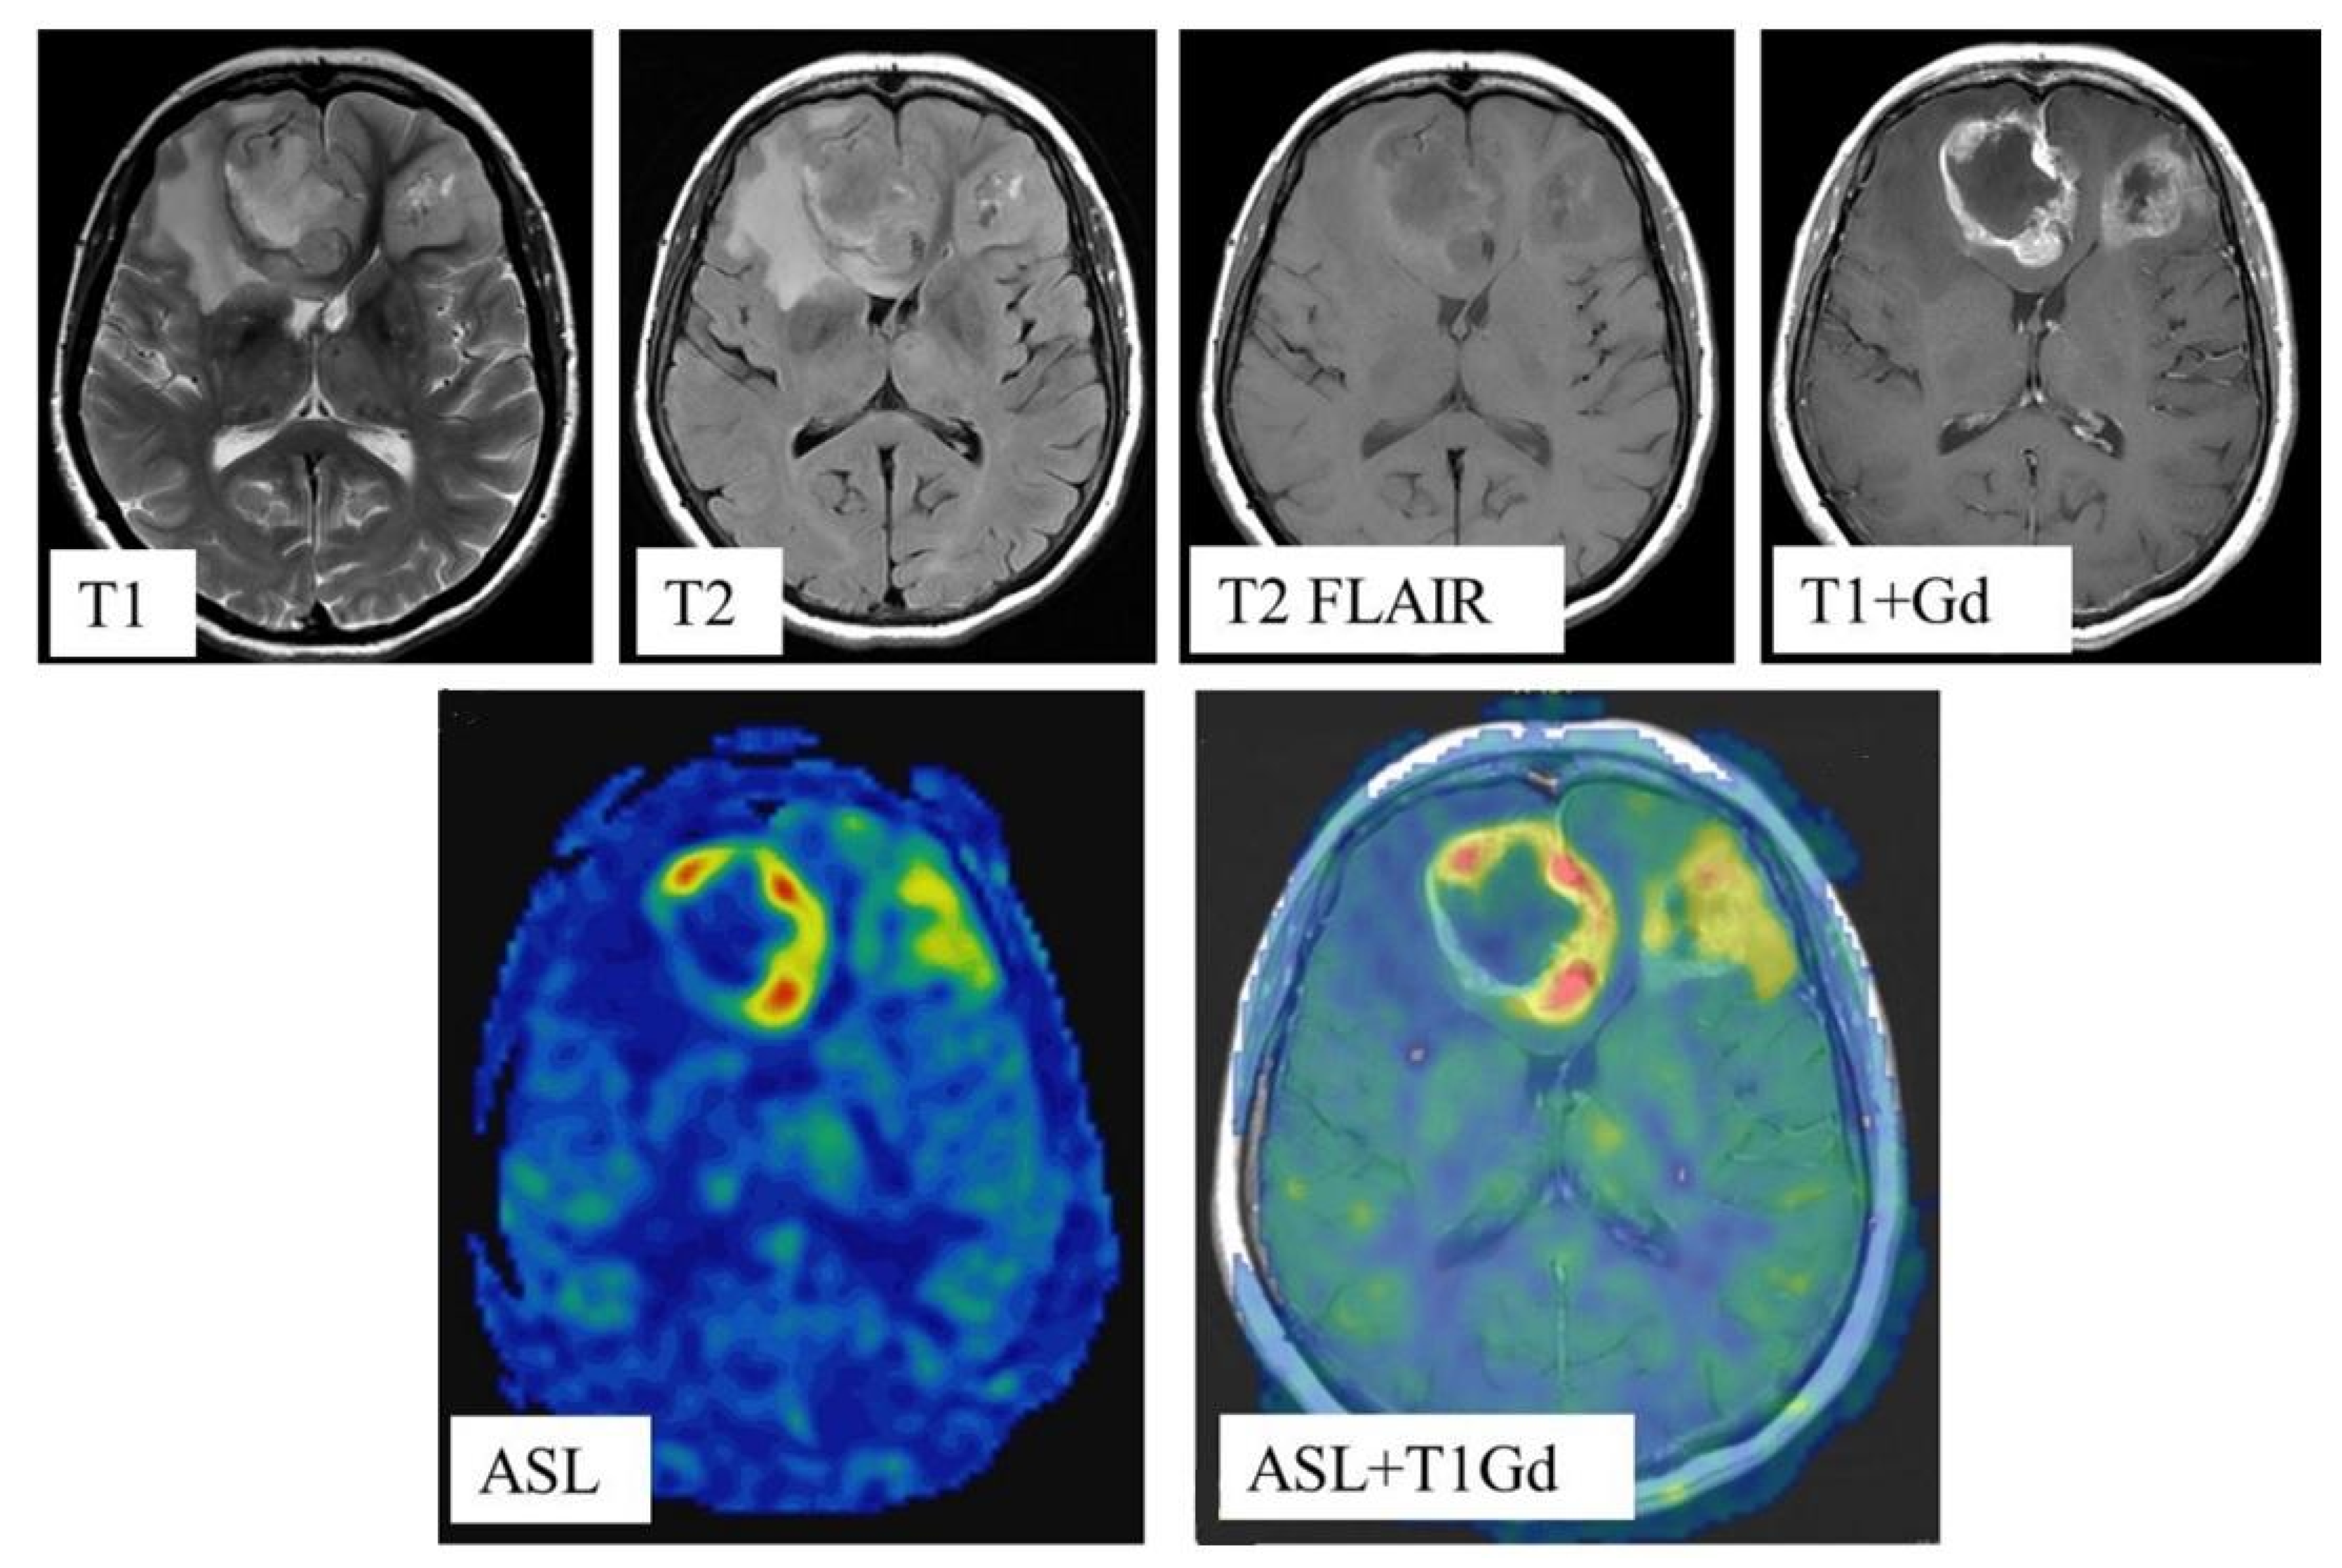

Postprocessing of the obtained data was performed using the ReadyView software package (GE Healthcare). To measure blood flow in the tumor, a region of interest (ROI) with an area of 20 mm2 ± 10 mm2 was designated in the zone with the highest CBF value (determined on color blood flow maps). In the designated ROI, the average value of TBF was calculated. To eliminate individual blood flow differences, we normalized TBF (nTBF) to blood flow in the intact white matter of the contralateral hemisphere semioval center. For this purpose, ROI with the same area (20 mm2 ± 10 mm2) as the tumor ROI was placed—Figure 1. To obtain normalized values, the obtained TBF data were divided by the blood flow in the semioval center (nTBF = maxTBF/CBF of the intact white matter of the contralateral hemisphere semioval center).

Figure 1.

Blood flow measurement on parametric maps.